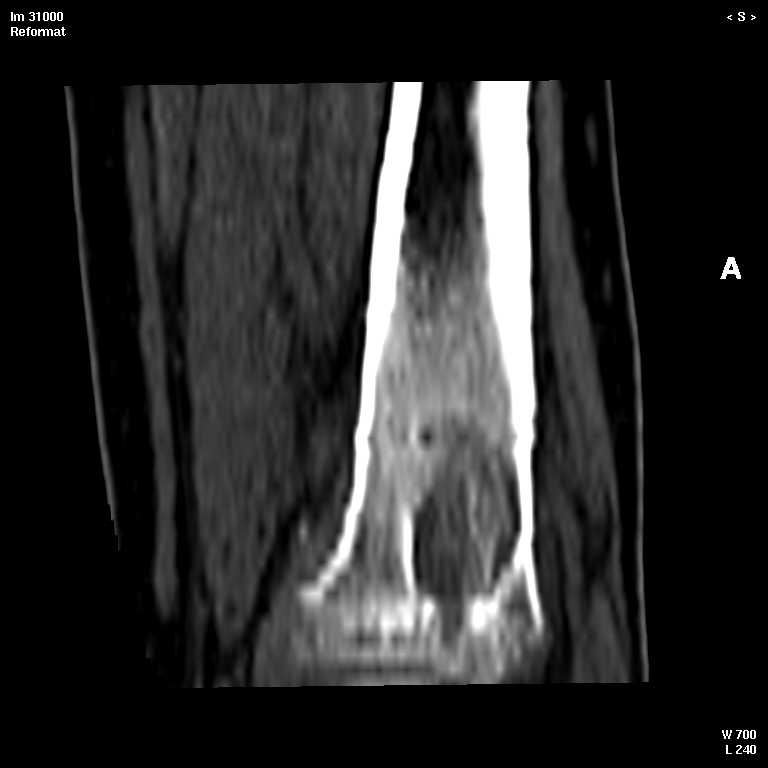

КТ изображения передаю на мой взгляд самые демонстративные. Их любезно записал коллега,

проводивший исследование в другом городе.

Прошу прощения за немного некоректную отправку КТ-снимков но по другому не получается :)